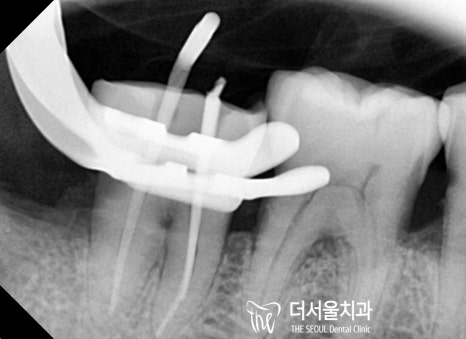

하악 신경치료를 진행한 다음,

오염된 치수를 제거하고 근관의 길이를 측정했습니다.

전치부

구치부

이후 소독 과정을 거친 뒤,

뿌리 끝부분부터 빈 공간이 남아있지 않도록

밀봉을 도와드렸습니다.

자, 여기서 Point!

뿌리 끝까지 확실하게 밀봉하는 것이 중요합니다.

이 과정의 결과를 좌우할 수 있는 관건이 되는데요.

만약 뿌리 끝까지 채워지지 않았다?

그러면 또 다른 염증이 생기거나,

같은 곳에 병소가 재발하는 일이 생기게 되죠.

전치부 / 구치부

숨어있는 미세 근관까지 빼곡하게 채워주었습니다.

파노라마 사진을 보면 뿌리 끝까지 채워진 모습을 볼 수 있네요.